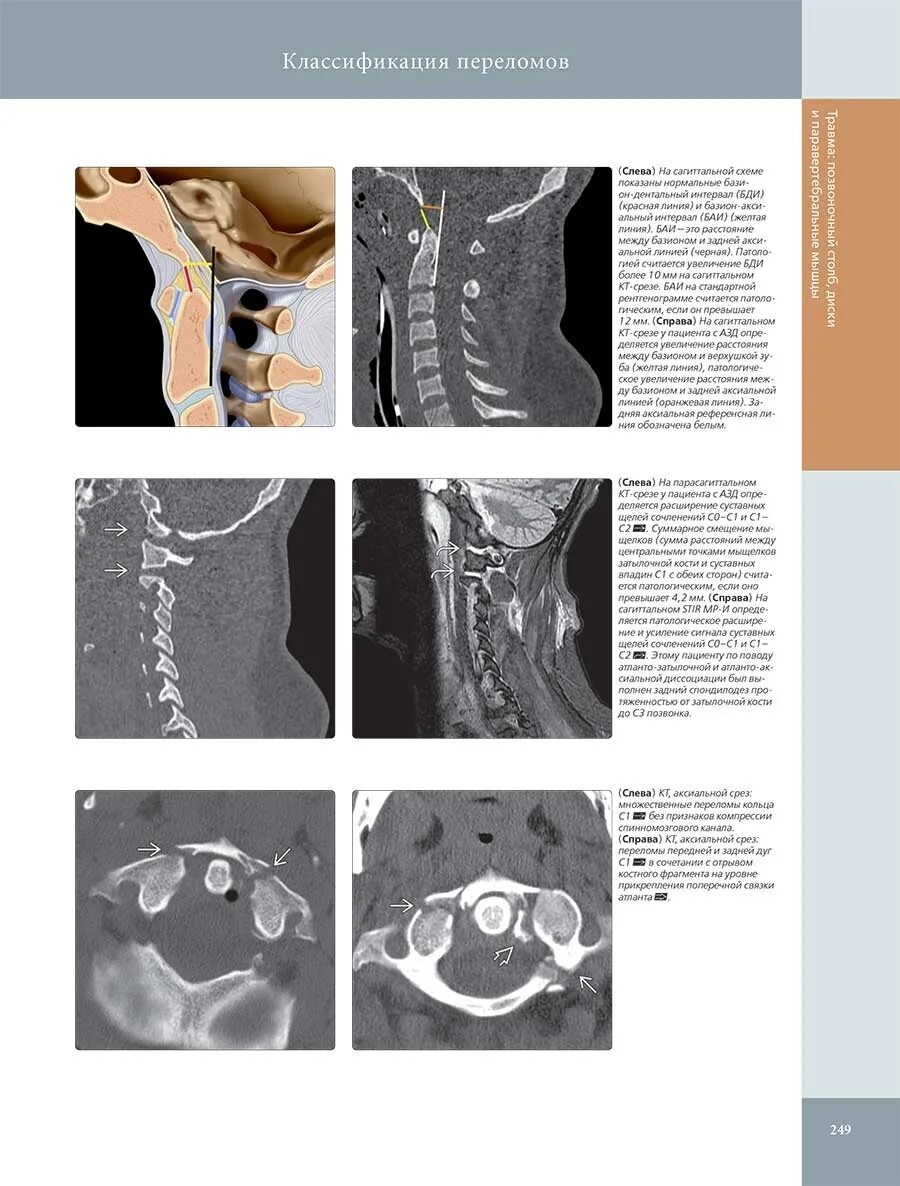

Классификация лучевой диагностики